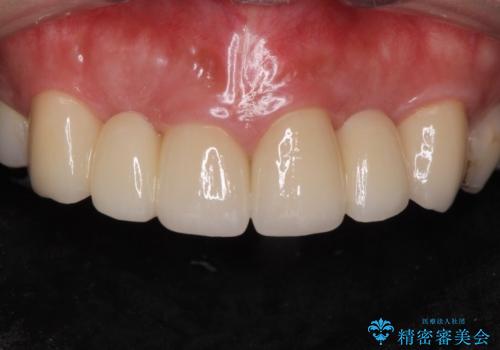

綺麗な被せ物が入りました。

最終的な被せ物は抜歯を行なってから半年経ってから形を整えて型取りを行います。

- ジルコニアクラウンスタンダード・仮歯 13.2万円×6 左上3精密根管治療(リトリートメント)・ファイバーコア 12.1万円費用は治療当時の料金となります